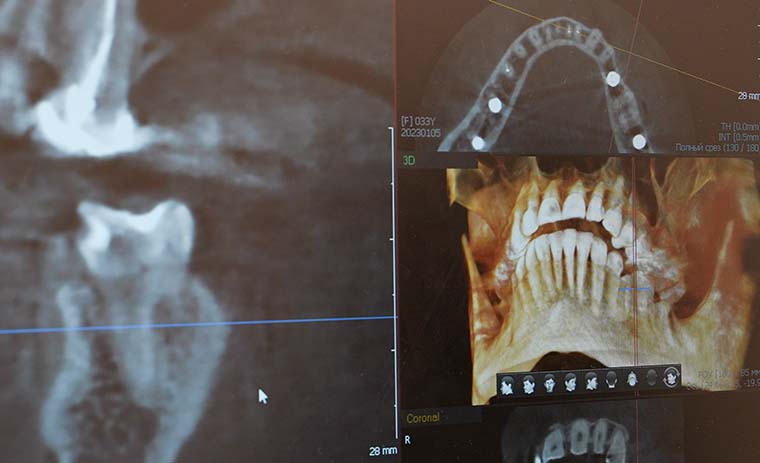

- Рентгенография: Рентгеновские снимки позволяют оценить состояние костей и выявить переломы или деформации.

- Денситометрия (DEXA-сканирование): Этот метод позволяет точно измерить плотность костной ткани.

Результаты этих исследований помогут ветеринару поставить точный диагноз и разработать индивидуальный план лечения для вашего хаски.